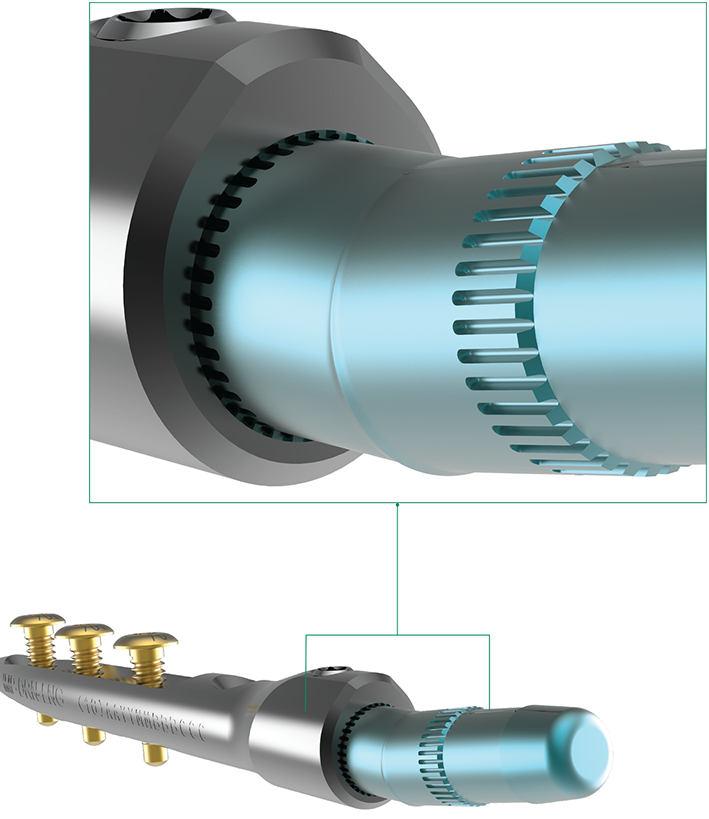

Wrist intramedullary nail – IMPLATE ® – Skeletal Dynamics

IMPLATE® Wrist Arthrodesis Nail – Skeletal Dynamics